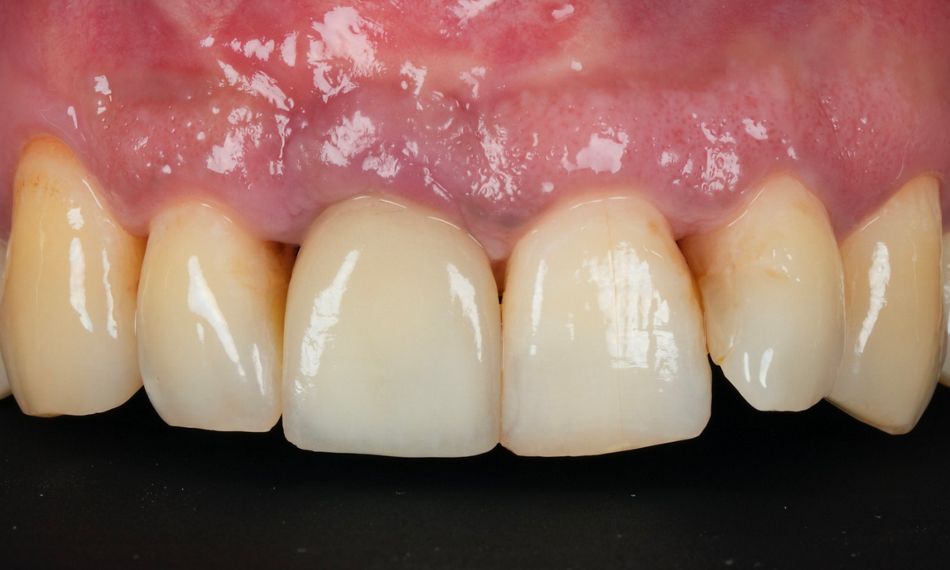

A 45-year-old male patient referred for treatment of peri-implantitis presented with recurrent inflammation, bleeding, and discomfort around the implant at tooth #11. His primary concern prioritized health over esthetics, with a strong desire to preserve the 1.5-year-old implant, even though full bone regeneration was not expected due to the implant position. He had no identifiable risk factors such as systemic diseases or smoking. His dental history included generalized stage III, grade C periodontitis, and extraction of tooth #11 due to a root fracture, followed by immediate implant placement and provisionalization (Fig. 1).

Fig. 1

The referring dentist placed the definitive crown. The patient was very pleased with the result (Fig. 27)

Fig. 27